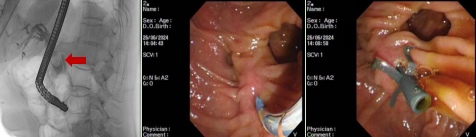

患者,男,85岁,主因“发现胆总管结石伴胆管炎,胆囊内胆汁淤积2个月”入院,曾就诊我院介入治疗科行PTCD及胆囊造瘘治疗,既往心肌梗死行冠脉支架置入、肺结核病史、肺大疱手术史,患者再次入院行内镜下逆行胰胆管造影术并胆总管取石治疗。

患者,男,74岁,主因“皮肤黄染5天”就诊我科,腹部CT提示肝外胆管及胆囊壁增厚伴强化,性质待定。既往高血压、冠心病病史,心脏搭桥术后、COPD病史。行内镜下逆行胰胆管造影发现胆总管上段有巨大结石,胆道梗阻,给予内镜下球囊扩张及胆总管取石治疗。

老年男性患者,主因“上腹部疼痛1天伴恶心呕吐”入院,既往糖尿病病史。腹部CT提示胆囊结石,胆总管内高密度灶,考虑胆总管结石,行内镜下逆行胰胆管造影术并及胆总管取石治疗。